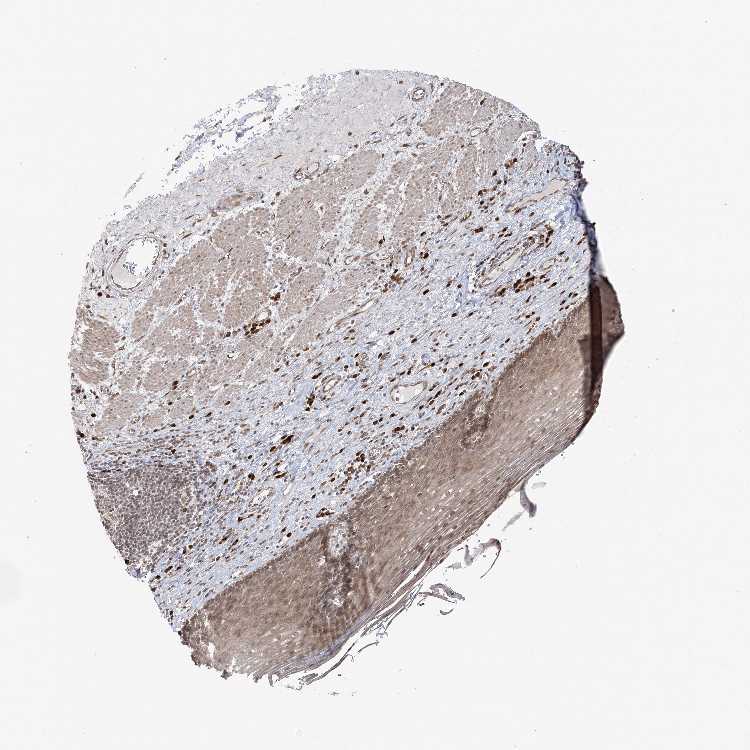

ESOPHAGUS - Antibody stainingi

Antibody staining in the annotated cell types in the current human tissue is reported as not detected, low, medium, or high, based on conventional immunohistochemistry profiling in selected tissues. This score is based on the combination of the staining intensity and fraction of stained cells.

Each image is clickable and will lead to virtual microscopy that enables deeper exploration of all samples and also displays staining intensity scores, fraction scores and subcellular localization as well as patient and tissue information for each sample.

Antibody HPA047139Antibody HPA050539Antibody CAB034442Antibody CAB037251

Squamous epithelial cells LowNot detectedLowMedium